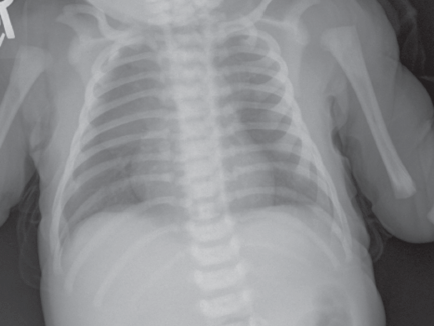

Lateral chest radiograph showed a prominent lucency in the anterior cardiophrenic angle (Figure 1). On anteroposterior radiograph, a small, thin rim of lucency was visible along the right heart border.

Figure 2. Anteroposterior radiograph showing a thin, lucent rim along the right heart border, consistent with a small pneumopericardium. No halo sign or continuous diaphragm sign is present, reflecting a minimal amount of air in the pericardial sac.

The diagnosis of pneumopericardium is confirmed with chest radiography: Anteroposterior view radiographs will show air surrounding the heart shadow (the halo sign) and outlining the superior border of the diaphragm (the continuous diaphragm sign).2